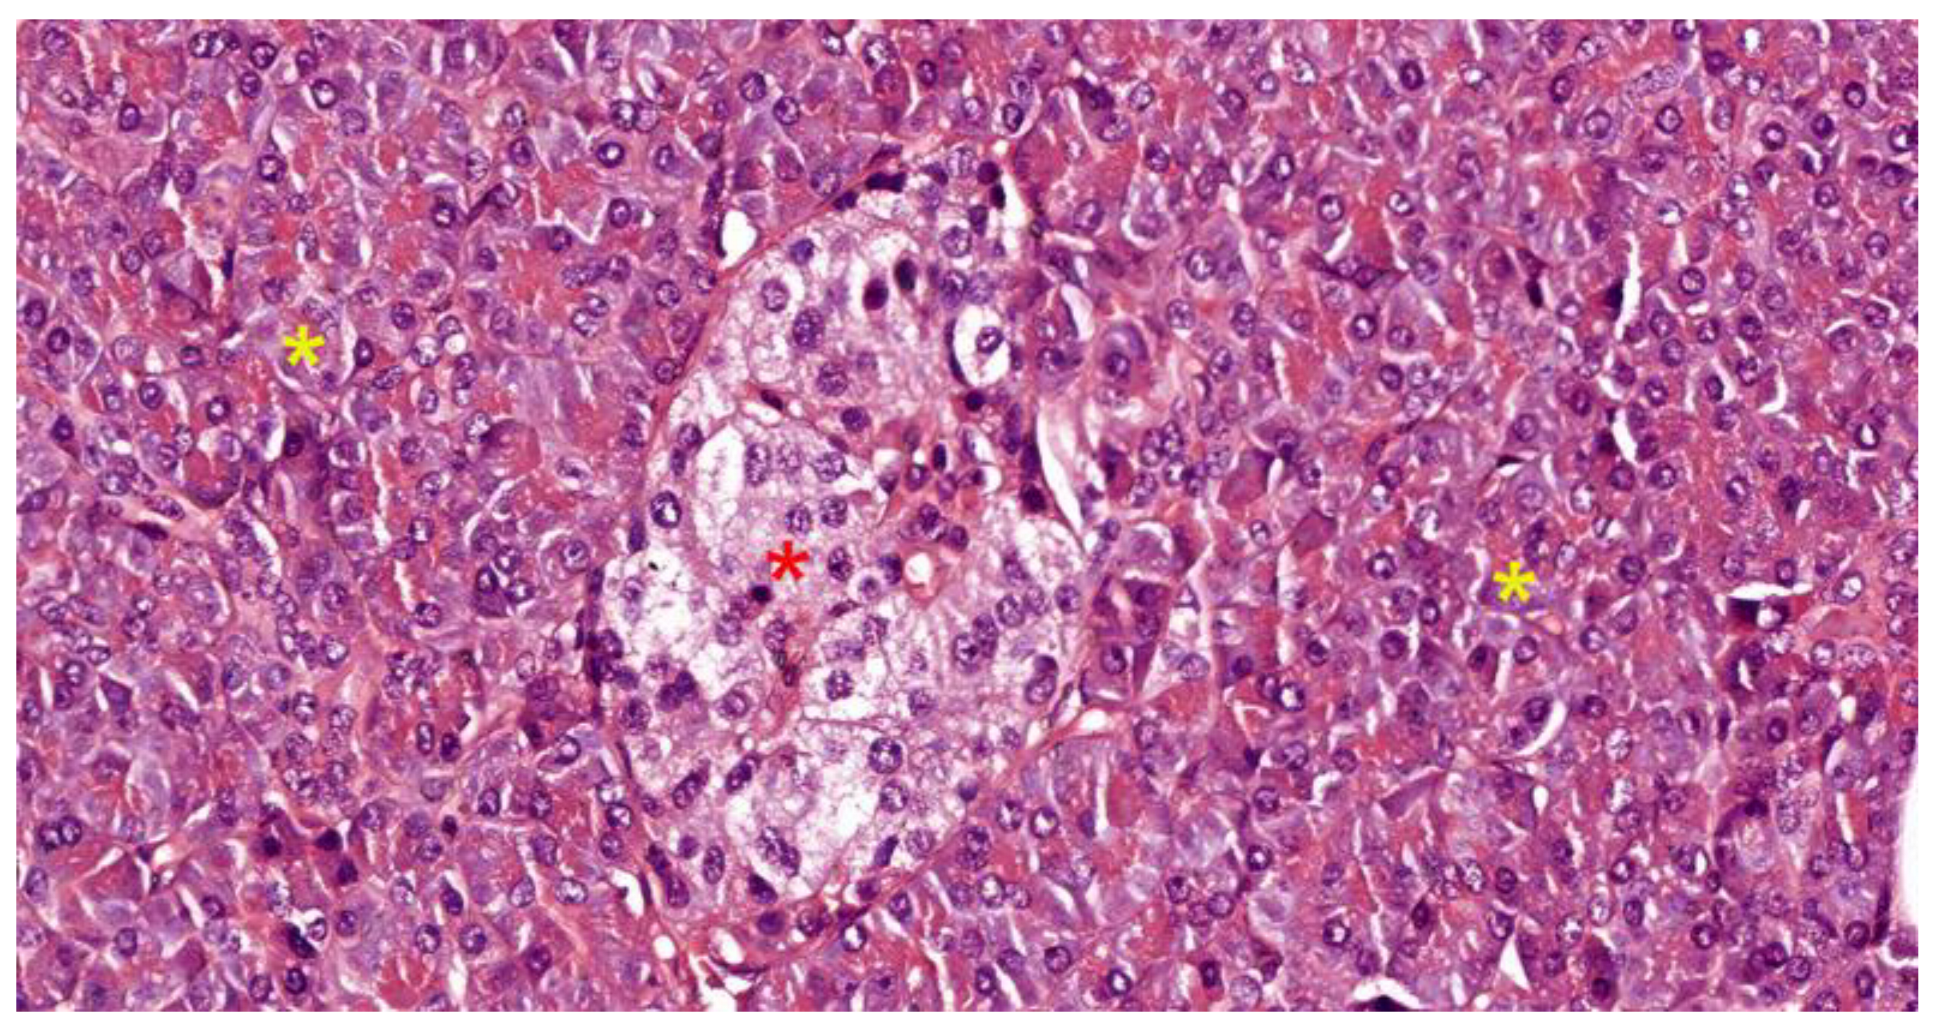

The Endocrine Pancreas